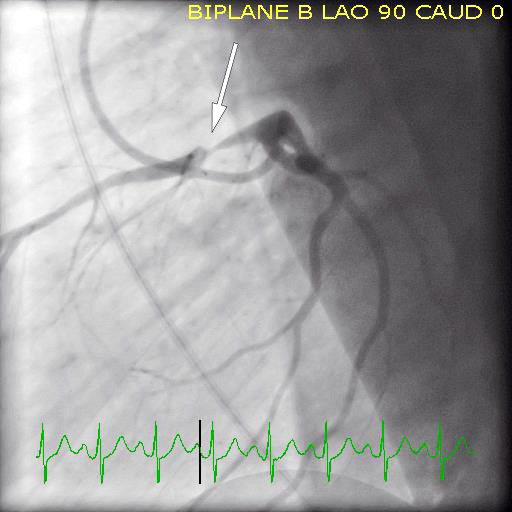

Pasienten var vedvarende smertefri etter initial behandling i akuttmottaket. Man besluttet derfor i samråd med vakthavende overlege ved nærmeste døgnåpne senter for invasiv kardiologi å avvente trombolytisk behandling. Det ble umiddelbart iverksatt overflytning til sykehus med mulighet for invasiv koronarutredning, og han ankom dit tre timer senere (det vil si fem timer etter symptomdebut). Koronar angiografi utført kort tid etter ankomst viste en svært trang stenose i proksimale fremre venstre koronararterie (figur 2). Arterien var ikke okkludert på undersøkelsestidspunktet. Det ble ikke funnet patologi i de andre koronararteriene. Stenosen ble vellykket behandlet med perkutan koronar intervensjon (PCI) med implantasjon av en medikamentavgivende stent.